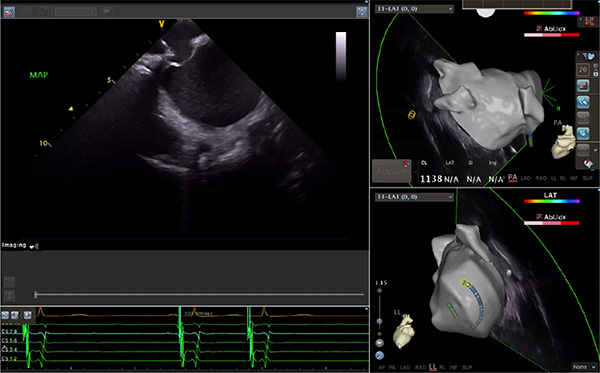

超聲心動圖技術(shù)包括常規(guī)經(jīng)胸超聲(TTE)、經(jīng)食管超聲(TEE)、心腔內(nèi)超聲(ICE)、超聲聲學(xué)造影(MCE)、三維超聲心動圖等,ICE是一種新興技術(shù)——將微型的換能器安裝在心導(dǎo)管的尖端,經(jīng)由外周血管輸送至心腔內(nèi)部,換能器發(fā)射聲波,對心臟及其鄰近組織進行實時高質(zhì)量成像和(或)血流動力學(xué)測定的超聲成像技術(shù)?;诓煌募夹g(shù)原理,心腔內(nèi)超聲導(dǎo)管被分為兩類:機械旋轉(zhuǎn)式超聲導(dǎo)管和相控陣超聲導(dǎo)管。目前,臨床上主要應(yīng)用的是相控陣超聲導(dǎo)管,ICE成像通過術(shù)者旋轉(zhuǎn)導(dǎo)管及操縱導(dǎo)管手柄上的兩個旋鈕來完成。

ICE門檻高、集成了超聲和圖像處理最前端的技術(shù),是當(dāng)前內(nèi)窺超聲方向最挑戰(zhàn)的領(lǐng)域。不同于傳統(tǒng)接觸式三維重建方法會產(chǎn)生假腔,影響術(shù)者對靶點或結(jié)構(gòu)的判斷,心腔內(nèi)超聲(ICE)可直接顯示心臟結(jié)構(gòu),有助于理解心臟內(nèi)各部位之間的解剖關(guān)系,不僅具有實時成像、并發(fā)癥監(jiān)測以及良好的耐受性,同時以股靜脈入路,無需全麻或深度鎮(zhèn)靜,日益成為心臟介入手術(shù)中重要輔助工具,被譽為心臟介入醫(yī)生的“黃金眼”。心腔內(nèi)超聲可用于多種心臟介入手術(shù),潛在患者群體龐大,動脈網(wǎng)測算我國心腔內(nèi)超聲導(dǎo)管市場空間或?qū)⒊?00億元,具有廣闊前景。

隨著心腔內(nèi)超聲的應(yīng)用更廣,性能也在逐漸優(yōu)化,已從二維成像轉(zhuǎn)變?yōu)?strong>三維成像,極大增強了引導(dǎo)及可視化能力。二維心腔內(nèi)超聲支持雙平面或三平面成像,可顯示兩個或三個不同的平面視圖,但醫(yī)生需將這些圖像在腦海中重新構(gòu)建為三維解剖結(jié)構(gòu)。三維心腔內(nèi)超聲則可直接呈現(xiàn)三維解剖結(jié)構(gòu)圖,便于醫(yī)生更輕松地開展手術(shù)。按照產(chǎn)品發(fā)展方向,預(yù)計心腔內(nèi)超聲還將向更清晰、精準(zhǔn)、多功能等方向發(fā)展。